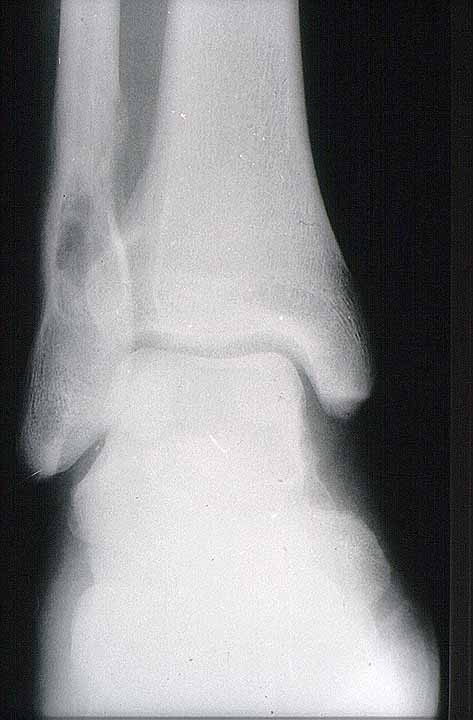

Figura 2